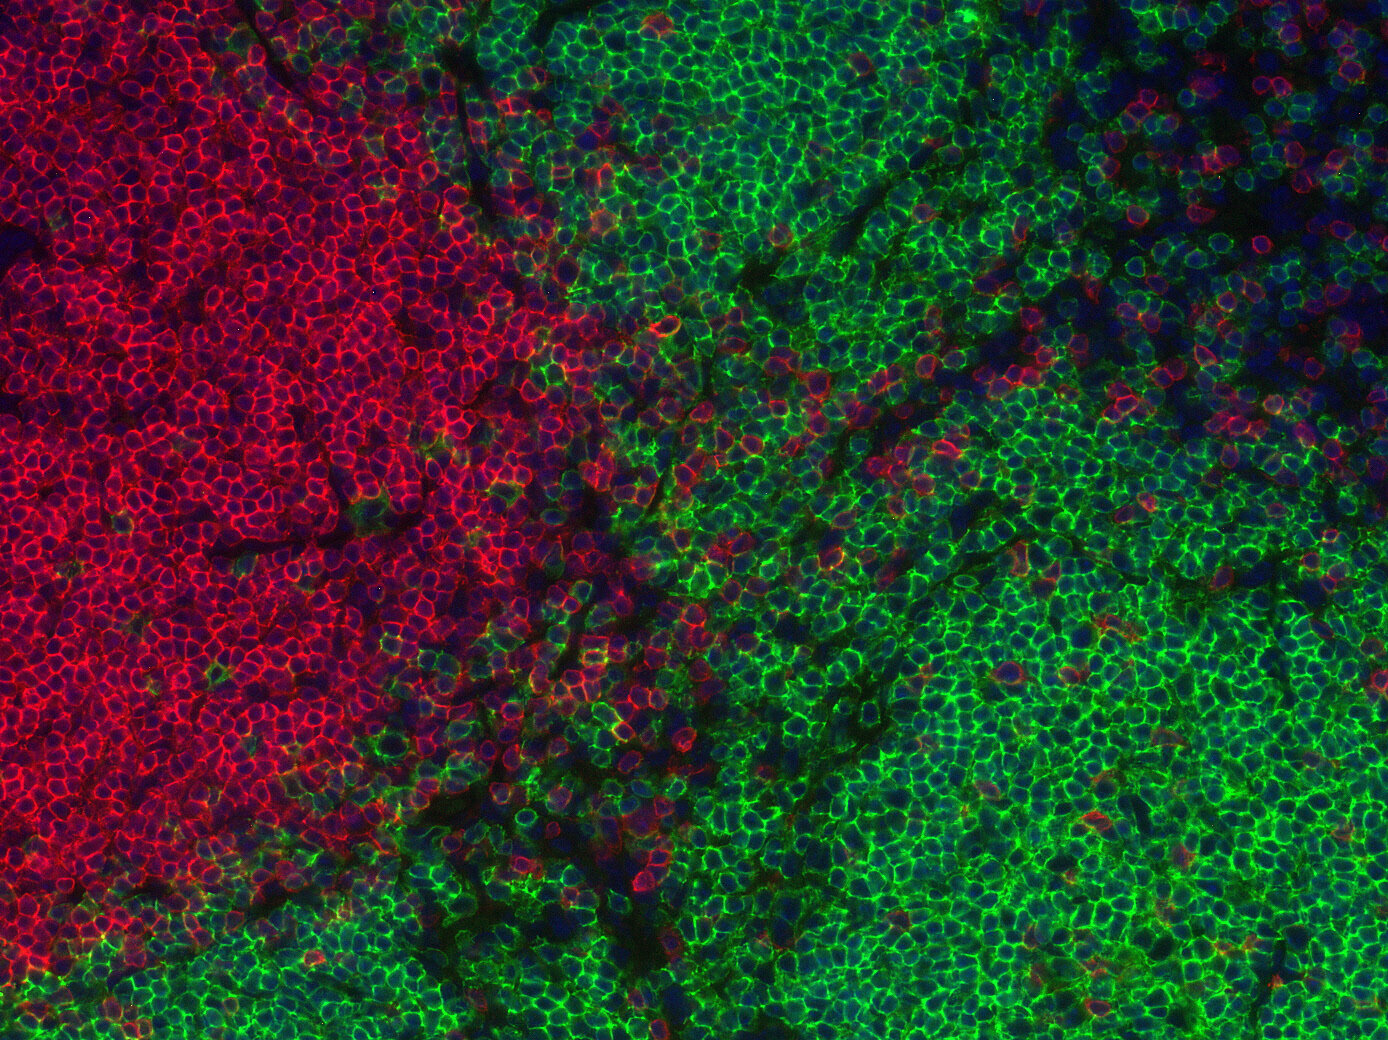

ICC: 1 : 1000 gallery

Immunocytochemistry (ICC) on 4% PFA fixed cells. Immunoreactivity is usually revealed by fluorescence. Some antibodies require special fixation methods. For details, please refer to the “Remarks” section.